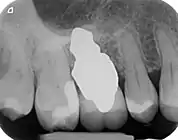

RAIs are custom made to perfectly fit the tooth socket of a specific patient immediately after tooth extraction. Therefore every implant is unique. As an optimized root-form it is much more than a simple 1:1 replica of a tooth. Since it exactly fills the gap left after the tooth is extracted, surgery is rarely needed. The implant can be produced from a copy of the extracted tooth, an impression of the tooth socket, or from a CT scan or CBCT scan.[3] The advantage of a CBCT scan is that the implant can be produced before extraction. With the former methods, it takes one or two days to fabricate an implant.

A root analogue implant can be fabricated from zirconium dioxide (zirconia) or titanium. Successful titanium RAIs have been three-dimensionally printed as porous one-piece implants, using CAD software.[4] However, zirconia is the preferred material, because it is more esthetic in color, with no grey discoloration visible through gums.[5][1]